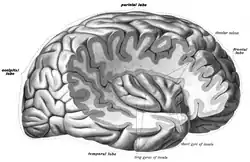

The insula of the right side, exposed by removing the opercula. | |

The insula of the left side, exposed by removing the opercula.

The insula of the left side, exposed by removing the opercula. Coronal section through anterior cornua of lateral ventricles.